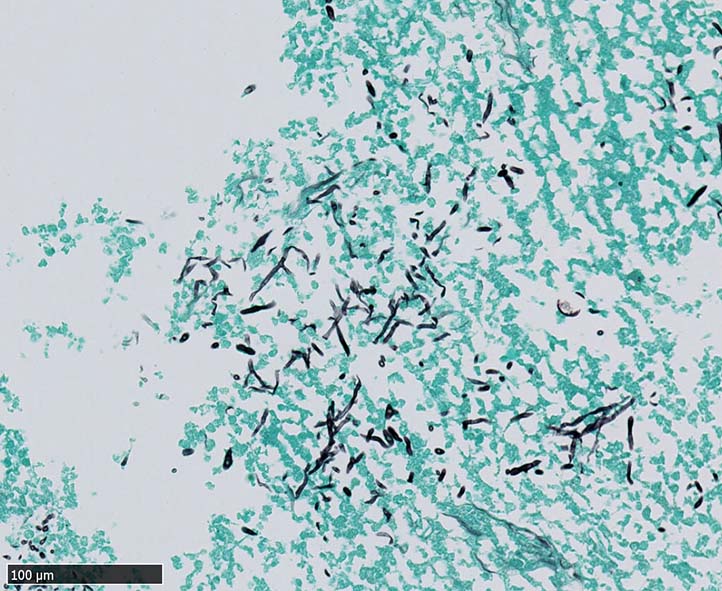

空洞辺縁の壊死部分に真菌菌体が認められた.

空洞辺縁には5~50μm径ほどの球状体(spherule)が形成され, 大型の球状体の一部は内部に2~10μm径ほどの内生胞子(endospore)を容れている. 内生胞子はPAS, Grocottで染色される.

本症例では空洞壁部分に球状体のほか多数の菌糸発育が観察された.

栄養型(菌糸および分節型分生子)と寄生型(内生胞子を多数容れた球状体)*1